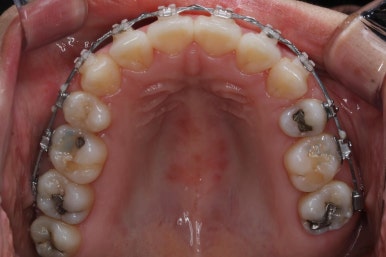

입안 모습입니다.

윗니와 아랫니 모두 각각 보면 가지런해 보이며 발치를 했던 자리도 거의 다 메워져서 양호해 보입니다. 훑어 보면 굳이 더 교정을 해야할 부분이 있을까? 싶겠지만 다음 사진을 보면 알 수 있습니다.

윗니를 봐도 미세하게 남았던 발치를 했던 공간이 없어졌습니다.

마무리 후에 다시 벌어질 수 있는 틈을 유지장치를 붙여 놓았습니다.